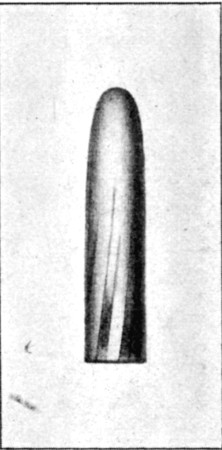

27. Normal Mauser Bullet83

34. Normal Lee-Metford Bullet89